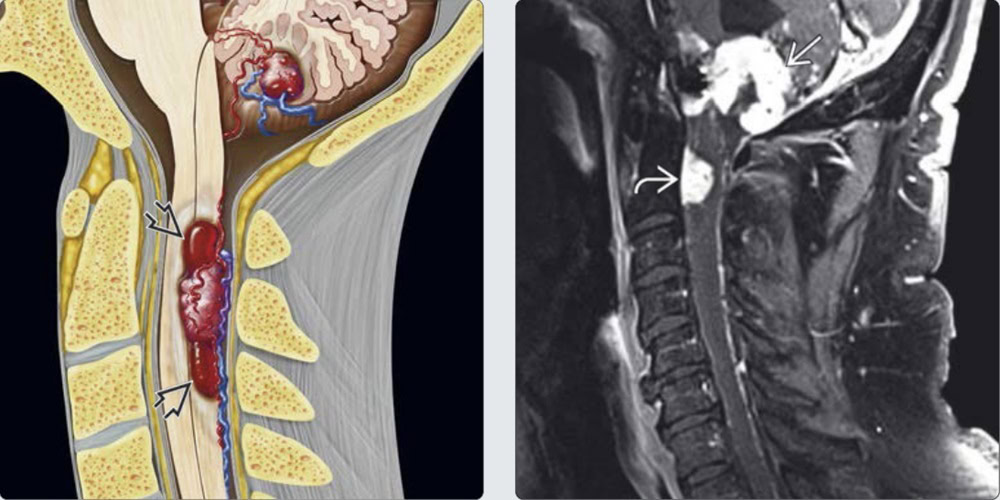

BỆNH LÝ HỆ THẦN KINH